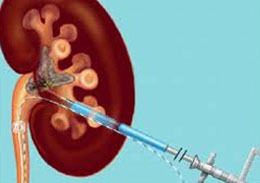

The percutaneous nephrolithotomy is a process of the surgery to remove kidneys stones. This action performed the help of a small 1cm incision through in the skin. Mostly this procedure uses when the stones size grow up to the 2cm. Generally this process used under the spinal anesthesia or general anesthesia.

The ureteroscopy is a procedure to a test. In this examination the ureteroscopy uses a small lighted tube for ureters test. The ureters are thin tubes, it is connected to the kidneys and the bladder, these thin tubes carries urine from the kidneys to bladder. By using an ureteroscopy the specialist can look a stone in the ureter and he can remove stone with the little basket at the ending of a wire inserted by an extra channel in the ureteroscopy.